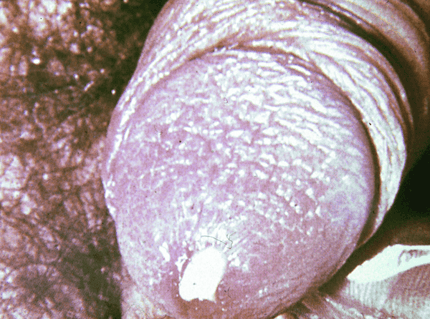

Syphilis in Men

Syphilis is a common bacterial infection that's spread through sexual intercourse.

Syphilis is easily cured with antibiotic medication, but can cause permanent damage if you are not treated immediately.

Untreated syphilis can lead to permanent problems like brain damage, paralysis, and blindness.

Syphilis is easily transmitted during sex when one partner have a syphilis sore in the anus or genitals or through kissing with an oral sore. The infection cannot be spread through casual contact, such as sharing foods, hugging, holding hands, coughing, or sitting on a toilet seat.

Syphilis symptoms in men appear as chancres or sores and most likely develop on the penis head or top of the shaft or on the scrotum.